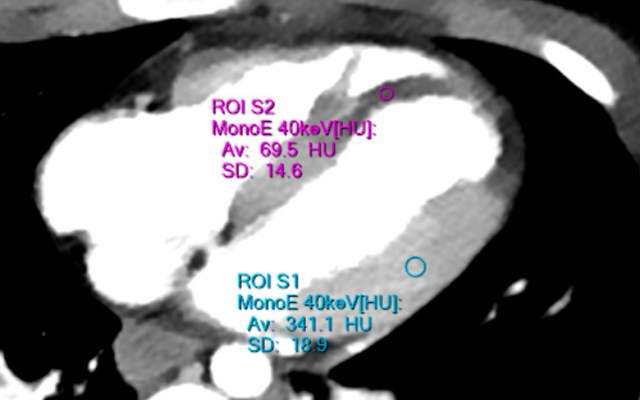

Let's look at a closer view, and also made easier to see using Spectral CT:

The very dark area at the septum and the apex of both ventricles is transmural ischemia. There is no contrast making it into this area which should be perfused by the LAD.

Notice the extremely dark area at the apex and apical part of the septum.